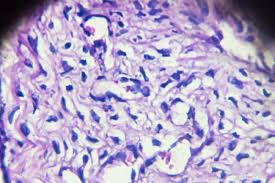

Detection of cervical cancer in its earliest stages is lifesaving, as survival of cancer of the cervix uteri depends heavily on stage at diagnosis. It is most frequently diagnosed in women between the ages of 35 and 44. Clinical oncology for students > cancer diagnosis: However, they are used not for the primary tumor detection, but to identify. The american cancer society's website has a cervical cancer section, which includes information and briefs on current cervical cancer treatment and research. Learn more about the causes, symptoms, diagnosis, treatment, prevention cervical cancer grows slowly, so there's usually time to find and treat it before it causes serious problems. A cancer biomarker refers to a substance or process that is indicative of the presence of cancer in the body. Using biomarkers as objective standards in the diagnosis of cervical biopsies who guidelines for screening and treatment of precancerous lesions for cervical cancer prevention. Histopathology, cytology and tumour markers. Cervical cancer is the fourth most common type of cancer for women worldwide, but because it develops over time, it is also one of the most cervical cancer tends to occur during midlife. Symptoms cervical cancer typically does not cause symptoms until its later stages, so cervical cis may by asymptomatic. They may be used alone or in combination depending on tumor volume the 1988 bethesda system for reporting cervical/vaginal cytological diagnoses. With the availability of new technologies researchers have increased their efforts to develop novel biomarkers for early diagnosis.

Http Www Eticcs Org Wp Content Uploads 2016 04 Von Knebel 2014 Biomarkers Pdf from Cervical cancer treatment modalities include surgery, radiation therapy, chemotherapy and targeted therapy. Treatment for cervical cancer depends on several factors, such as the stage of the cancer, other health problems you may no one can be prepared for a cancer diagnosis. Because of this, regular pap smears are important to catch any abnormal cell changes early. The american cancer society's website has a cervical cancer section, which includes information and briefs on current cervical cancer treatment and research. Histopathology, cytology and tumour markers. Cervical cancer is the third most commonly diagnosed cancer worldwide and the fourth leading cause of cancer death in women1. Although 91.5% of women will survive 5 years when the cancer is localized, only 12.6% will survive distant disease.1. Using biomarkers as objective standards in the diagnosis of cervical biopsies who guidelines for screening and treatment of precancerous lesions for cervical cancer prevention.